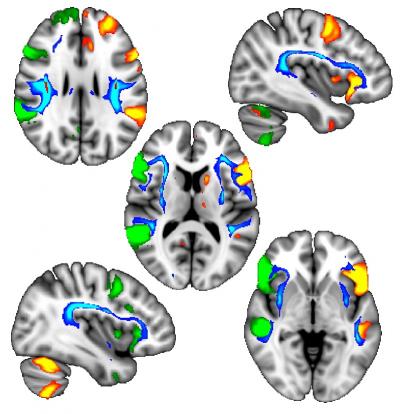

Using detailed brain imaging from approximately 10,000 of these participants, the researchers found that these genetic effects were associated with differences in brain structure in white matter tracts, which contain the cytoskeleton of the brain that joins language-related regions.

"We discovered that, in left-handed participants, the language areas of the left and right sides of the brain communicate with each other in a more coordinated way. This raises the intriguing possibility for future research that left-handers might have an advantage when it comes to performing verbal tasks, but it must be remembered that these differences were only seen as averages over very large numbers of people and not all left-handers will be similar."

"For the first time in humans, we have been able to establish that these handedness-associated cytoskeletal differences are actually visible in the brain. We know from other animals, such as snails and frogs, that these effects are caused by very early genetically-guided events, so this raises the tantalising possibility that the hallmarks of the future development of handedness start appearing in the brain in the womb."